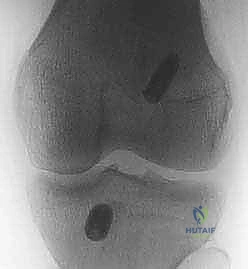

- الأشعة السينية (X-rays): تُطلب أولاً لنفي وجود أي كسور عظمية مصاحبة، مثل كسر "سيجوند" (Segond Fracture) وهو كسر قلعي صغير في الجانب الخارجي للقصبة يُعتبر علامة شبه مؤكدة لتمزق الرباط الصليبي.

- التصوير بالرنين المغناطيسي (MRI): هو المعيار الذهبي لتأكيد التشخيص. الرنين المغناطيسي لا يظهر الرباط المتمزق فحسب، بل يُظهر الإصابات المصاحبة التي لا تقل أهمية، مثل:

- تمزق الغضاريف الهلالية (Meniscal tears).

- كدمات العظام (Bone bruises) التي تحدث نتيجة ارتطام عظم الفخذ بالقصبة لحظة الإصابة.

- إصابات الأربطة الجانبية.